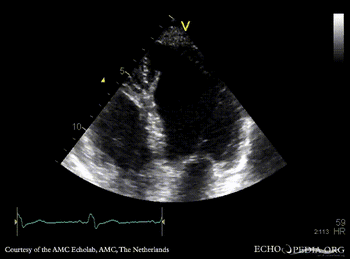

Abnormal motion of IVS

A4CH: abnormal motion of IVS in patient with LBBB